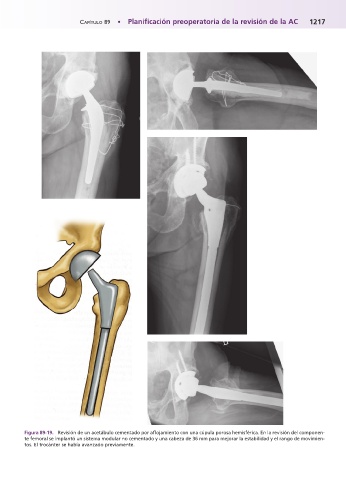

Figura 89-19.mRevisión de un acetábulo cementado por aflojamiento con una cúpula porosa hemisférica. En la revisión del componen-

te femoral se implantó un sistema modular no cementado y una cabeza de 36 mm para mejorar la estabilidad y el rango de movimien-

tos. El trocánter se había avanzado previamente.